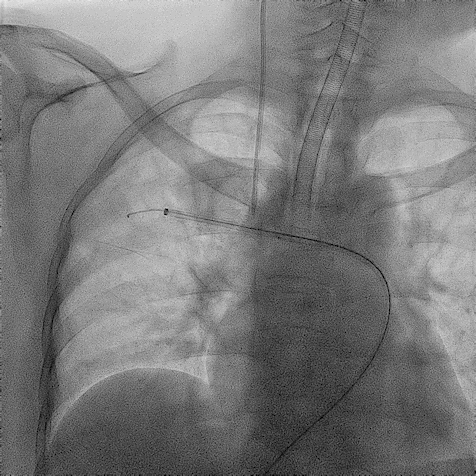

手术过程(一):

右股静脉穿刺,交换8 F-90 cm长鞘导入A3段,造影见A3段远端显影良好,中段动静脉瘘高速血流,可见“瘤槽”显影。